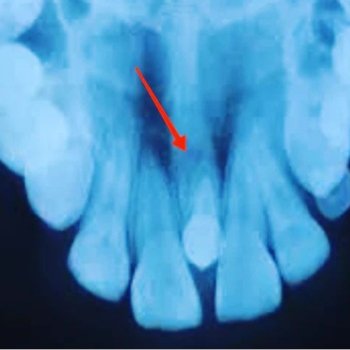

Normalmente, eles não se desenvolvem na dentição decídua, ou seja, não se manifestam nos dentes de leite da criança, aparecendo apenas com a formação da arcada permanente. Isso significa que sua formação ocorre entre os 6 ou 7 anos de idade. Na maioria dos casos, os dentes afetados são os incisivos centrais (dentes anteriores) e os molares (dentes posteriores). Os incisivos se desenvolvem em formato que lembra uma chave de fenda. Os dentes molares também podem apresentar um formato diferenciado, contando com um formato que lembra uma amora, com várias protuberâncias irregulares.

Além disso, outra característica dos dentes de Hutchinson é o maior espaçamento entre os dentes e a presença de sulcos em seu interior.